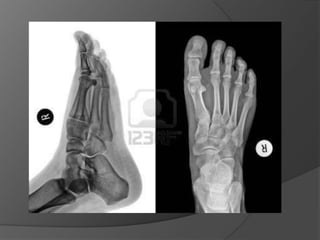

Fracturas De Pie

Una fractura de pie es una

fractura de cualquiera de los

huesos del pie.



Se puede producir una

fractura de pie en cualquier

hueso del pie, pero las

fracturas metatarsianas son

las más frecuentes.